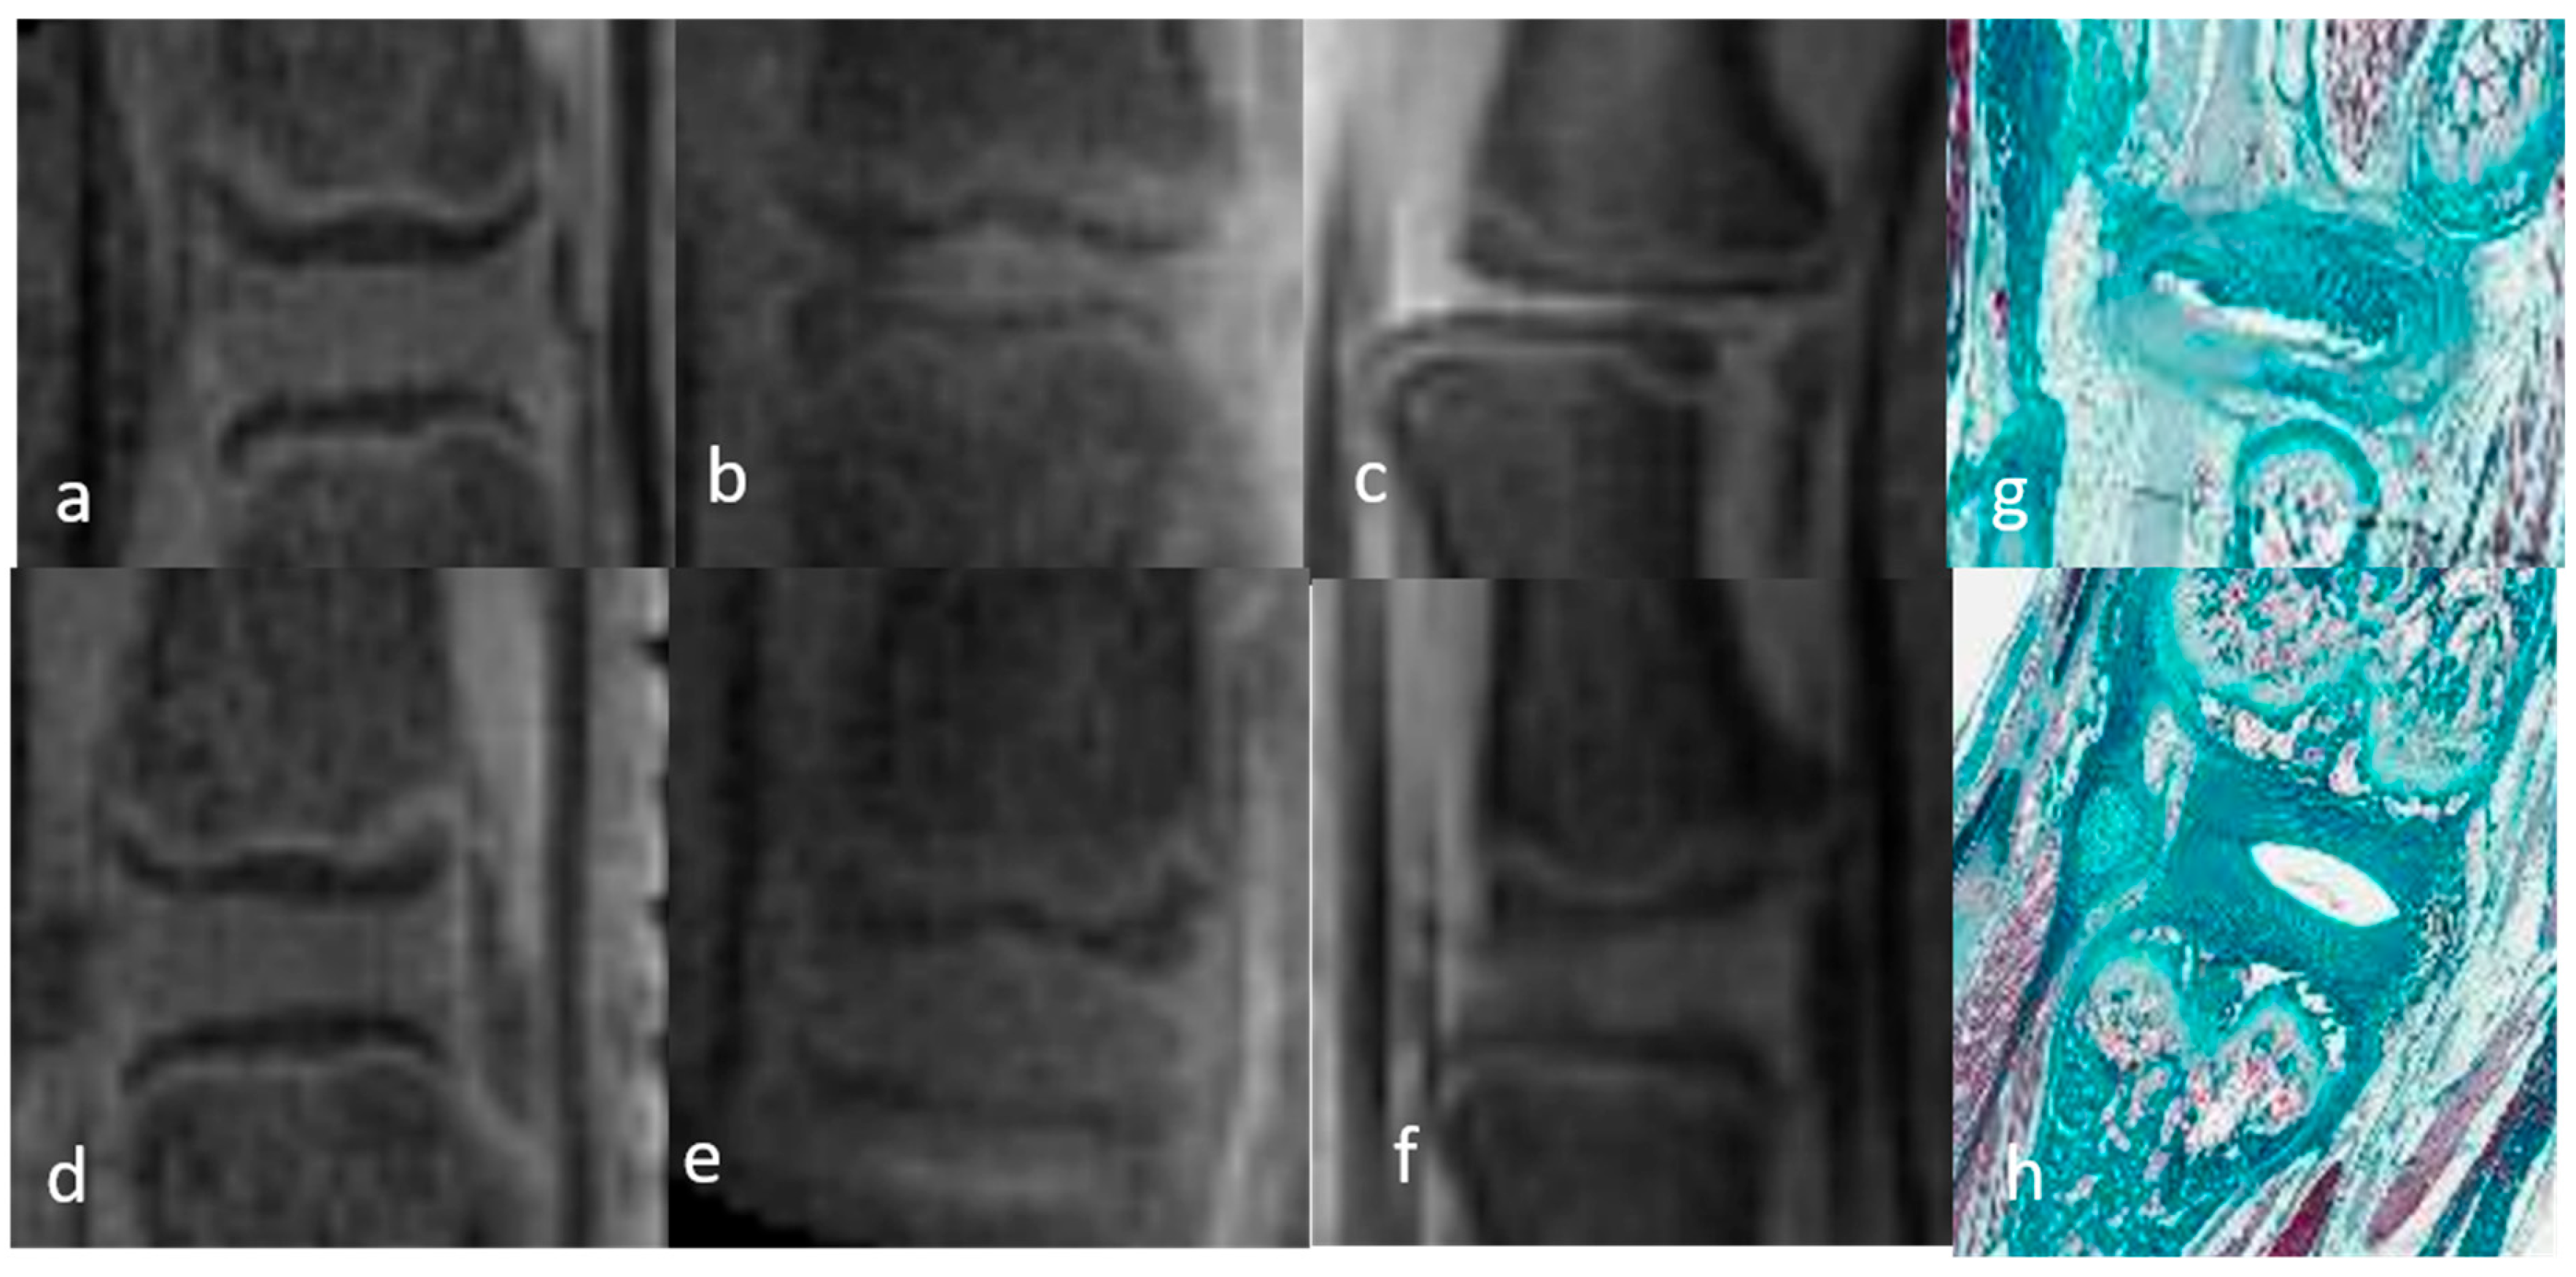

3.1.1. Qualitative Analysis of the Normal DVC (Table 1 and Table 2)

3.1.2. Qualitative Analysis of the DVC in DDD Rats (Table 3)